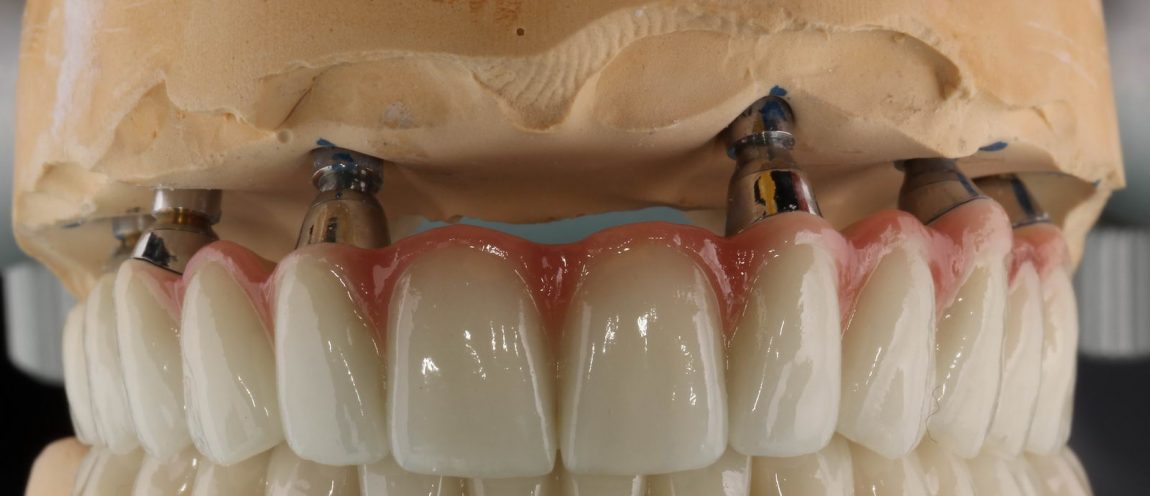

А можно пойти и дальше — поставить, четыре-шесть имплантов и сделать несъёмный: